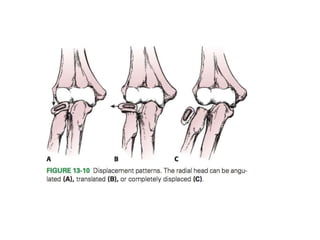

FIGURE SHOWS TYPE OF INJURY IN ELBOW

DISLOCATION

FIGURE SHOWS TYPEOF INJURY IN ELBOW DISLOCATION